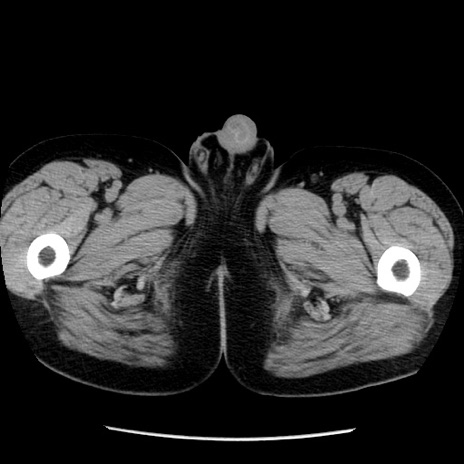

症例29(横断像)

【症例】40歳代男性

【現病歴】2日前から胃痛あり。徐々に周期的な激痛に変化した。本日になっても激痛があるため受診。

【身体所見】意識清明、BT 38-39℃台あり、腹部:膨満、やや硬、右下腹部に圧痛あり。

【データ】WBC 8500、CRP 23.26